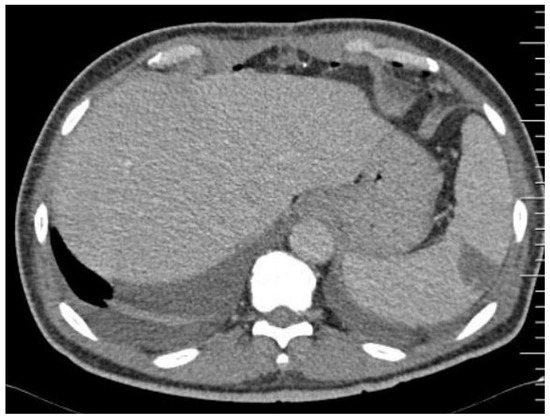

Splenic Embolism in Infective Endocarditis: A Systematic Review of the Literature with an Emphasis on Radiological and Histopathological Diagnoses

3. Results